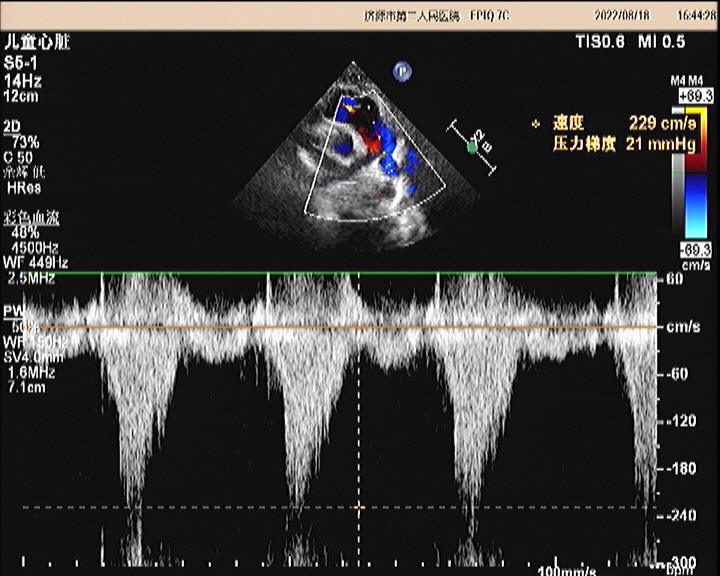

超声所见:各房室大小正常,肺动脉主干内径增宽,约20mm,左、右肺动脉内径分别约10mm、8.7mm,左、右肺动脉未见有狭窄,左肺动脉起始于主肺动脉的右侧并向左侧走行,右肺动脉起始于主肺动脉左侧向右走行。主动脉内径正常,搏动好。各瓣膜回声正常,肺动脉瓣开启可,关闭欠佳,余瓣膜启闭自如。房室间隔连续完整,室壁厚度及运动收缩幅度正常。CDFI:主肺动脉及左、右肺动脉前向流速增快。主肺动脉峰值流速:2.5m/s。左肺动脉峰值流速:2.2m/s。右肺动脉峰值流速:1.7m/s。肺动脉瓣口探及舒张期少量返流。

超声提示:1.左右肺动脉交叉 2.肺动脉主干内径增宽 3.肺动脉主干及左、右肺动脉前向流速增快 4.肺动脉瓣少量返流

(左肺动脉峰值流速)